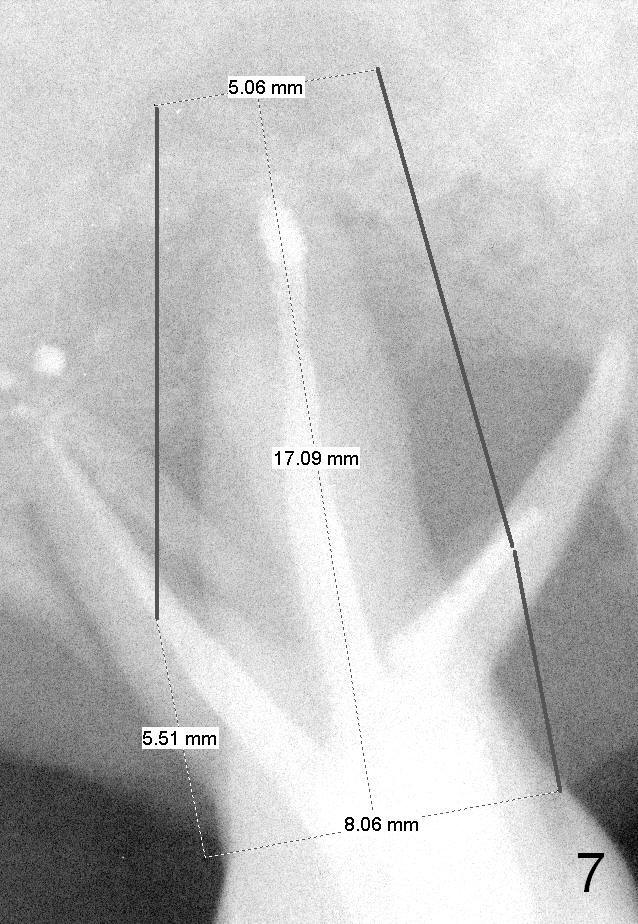

Two years post RCT, there is radiolucency around the MB root of the tooth #3 (Fig.1,2). Eleven days later, there is acute infection associated with MB and DB root fracture (Fig.3). According to the X-ray taken 11 days earlier (Fig.1,4), a long tissue-level implant (6x17 mm) is suitable for the site. In accordance with CBCT (coronal (Fig.5) and sagittal (Fig.6) sections) taken prior to RCT, a short bone-level implant (6.9x10 mm) is a more reasonable choice.

After extraction, the socket will be studied to determine where the bone is and where bony defects are for the site of the initial osteotomy. Start with 2 mm pilot drill or RT2, apparently ~ 6 mm depth, followed by reamers 2.5-3.5 mm and Tatum taps 4.5-7x17 mm (14 mm depth from gingival margin). Use a latch adapt with the torque wrench. Due to severe bone loss, the tap should not be too large (6 mm). If insertion torque is high and bone morphology is favorable, change to DIO taps and take necessary PAs to decide the length of the implant relative to the sinus floor and trajectory. If the depth is 10 mm or less, use SM; 12 mm UF. Based upon the most recent X-ray (Fig.3 with large lesion), the implant should be large and long (Fig.7: 7x17 mm).